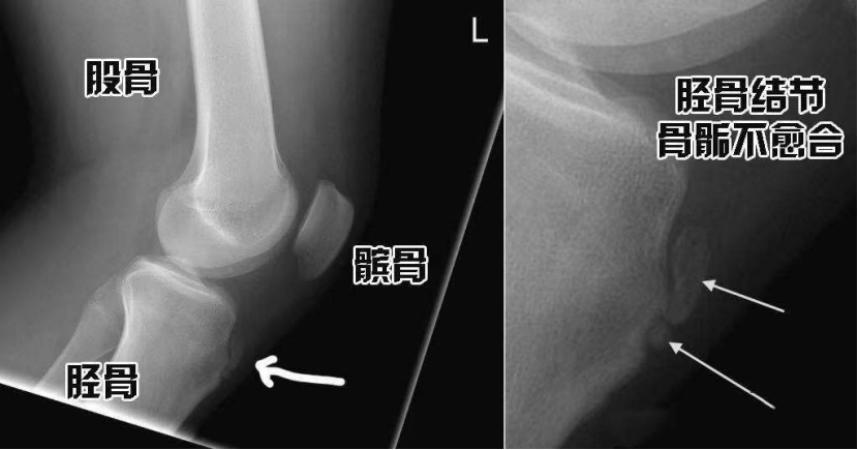

胫骨结节骨骺炎,又叫Osgood–Schlatter 病,简称OS病,是小腿骨(胫骨)近端生长板(骨骺)的水肿和炎症。青少年容易出现胫骨结节骨骺炎,因为此时骨骺没有闭合,反复跳跃导致髌腱反复牵拉胫骨结节,会损伤骨骺,引起疼痛肿胀的症状。

骨骺是骨在发育过程中软骨中出现的骨化点,大部分骨骼的生长发育发生于骨骼末端的骨骺处。骨骺强度较弱,容易受伤。OS属于自限性疾病,无需治疗,大部分OS病会自愈,症状也会消失。